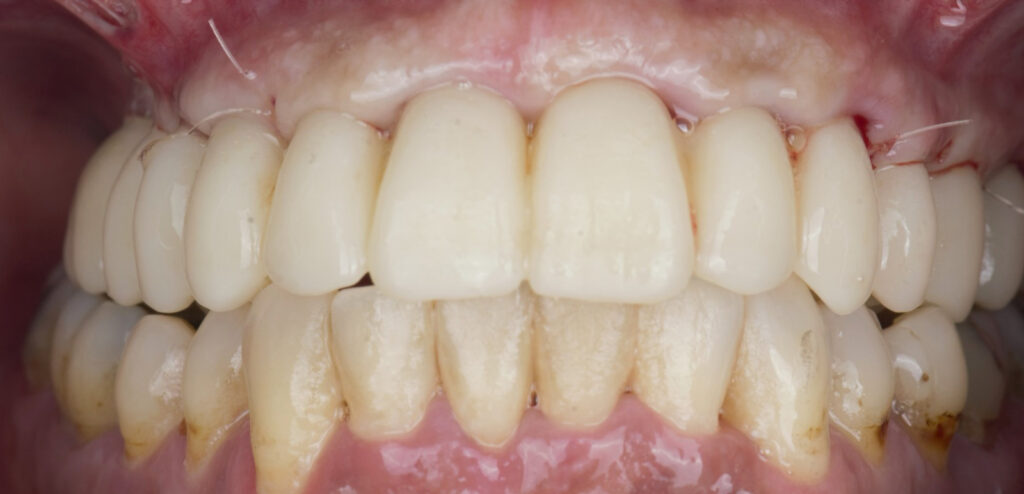

Caso clínico, Dr. José Amador Cabezas

Carga inmediata maxilar con cirugía guiada, registro fotogramétrico y provisionalización inmediata.

En este caso, el Dr. José Amador Cabezas aborda la rehabilitación completa de un maxilar superior comprometido por enfermedad periodontal avanzada, lesiones periapicales y múltiples restauraciones fallidas.

Tras la planificación protésicamente guiada y la colocación de implantes mediante cirugía guiada, se realizó el registro fotogramétrico con T-Marker sobre los Multi-Unit para capturar con precisión la posición real de los implantes y asegurar la pasividad de la estructura provisional.

Gracias a este flujo, el paciente pudo salir de la consulta con una prótesis fija inmediata el mismo día de la cirugía, iniciando así un proceso restaurador más preciso, más predecible y completamente integrado en el entorno digital.

La combinación de cirugía guiada, fotogrametría y carga inmediata permite un control preciso de la posición implantaria y una correcta pasividad protésica desde el primer día.